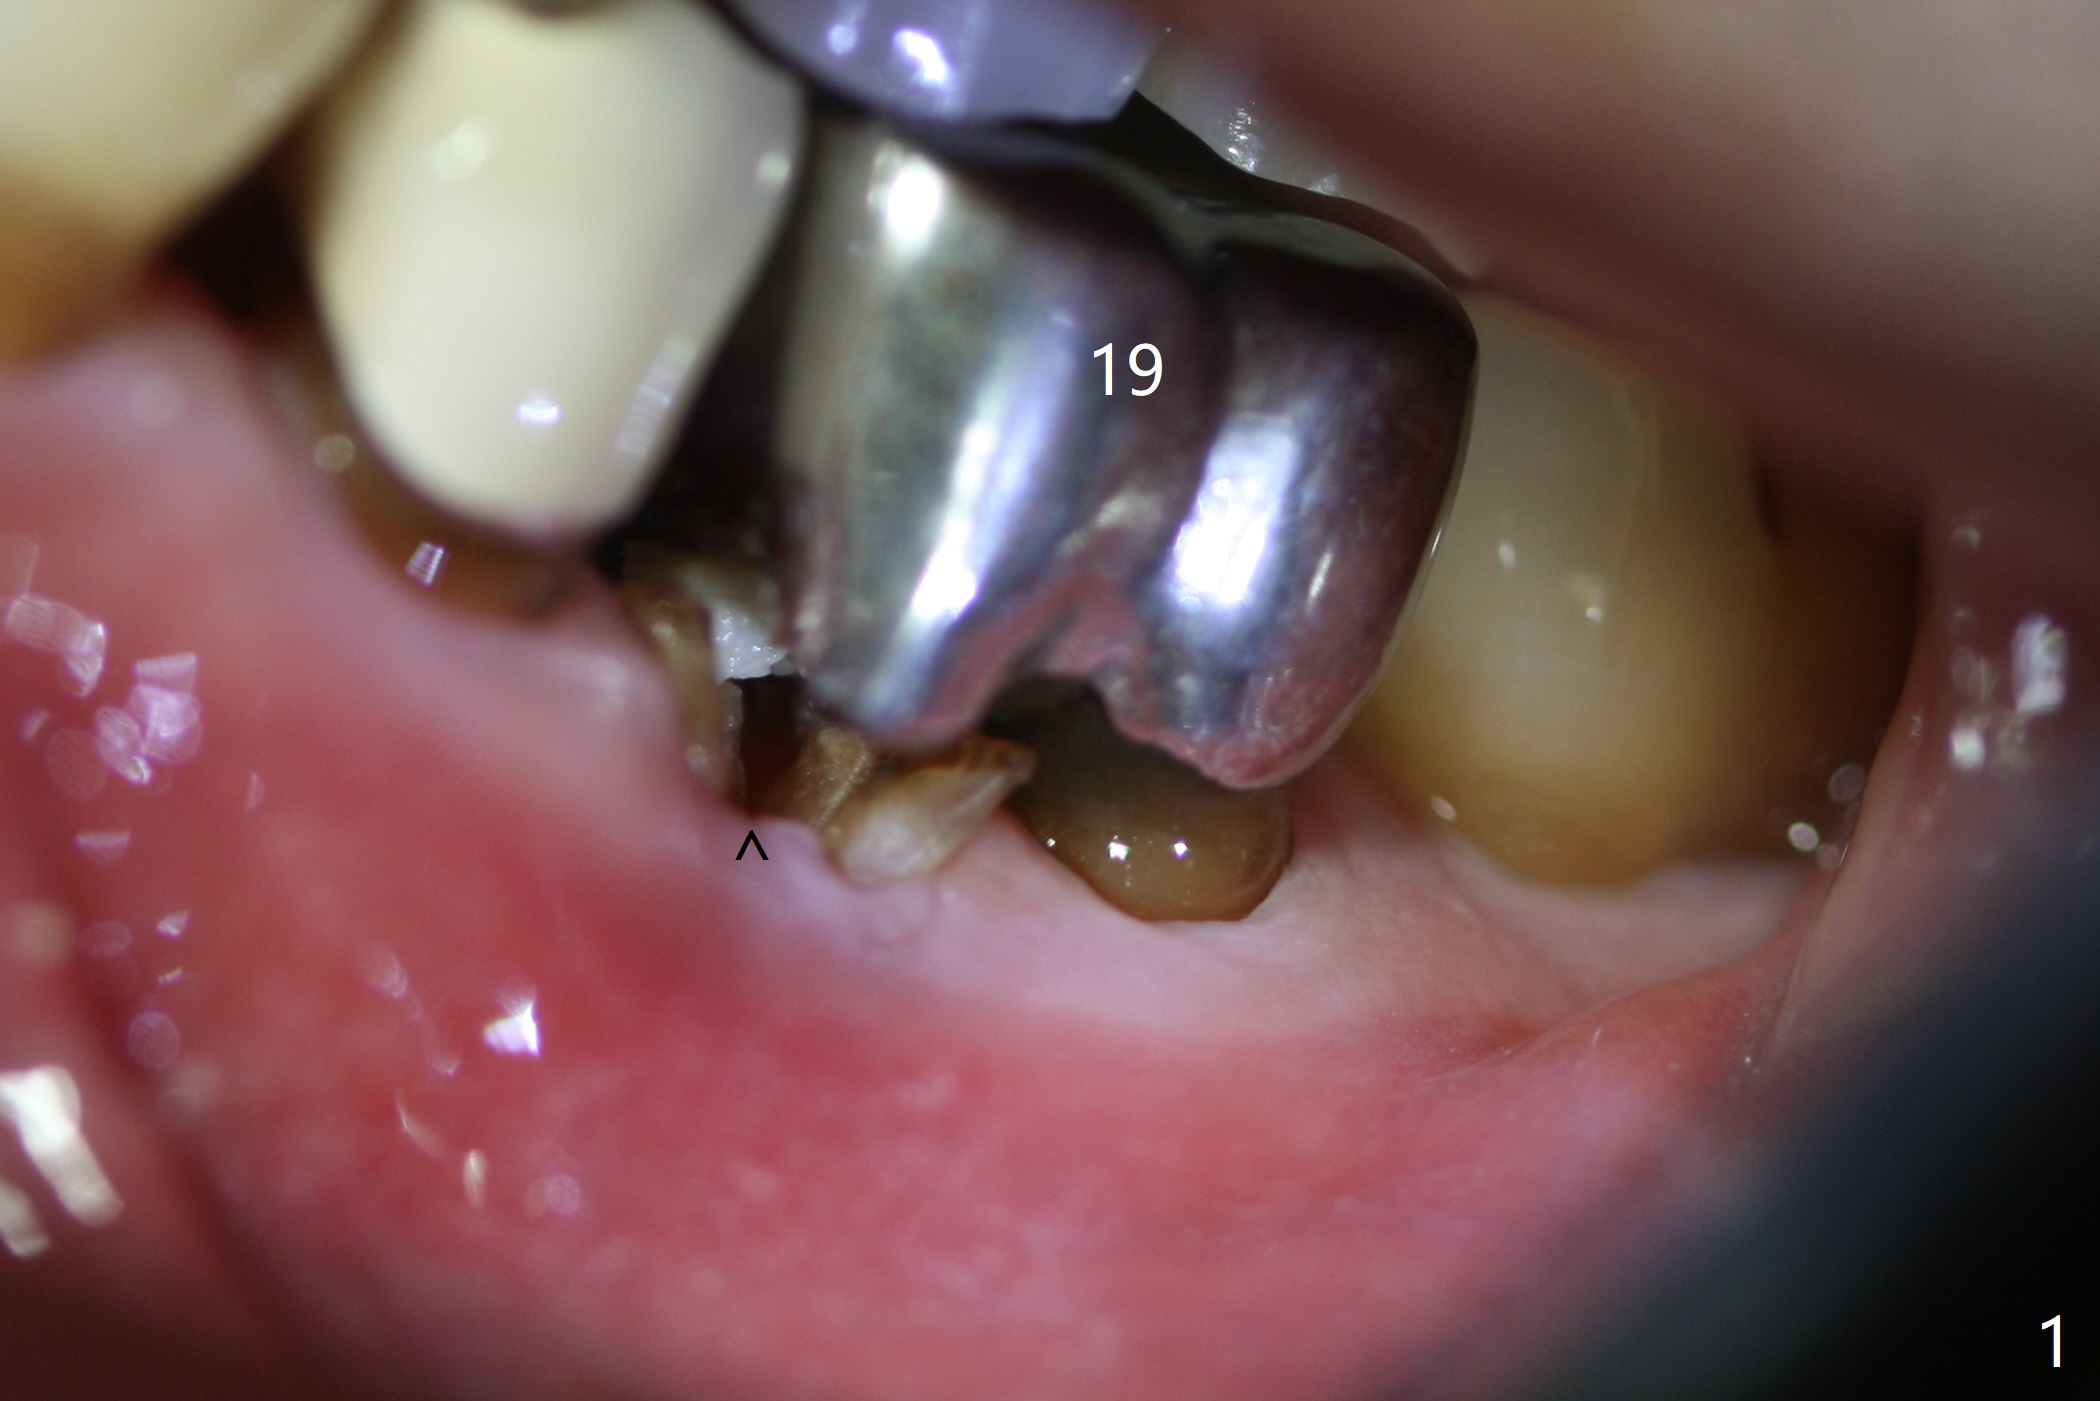

After extraction of the tooth #19 with mesial root fracture (Fig.1 ^) and curettage, the initial osteotomy in the septum is found to need to be distalized (Fig.2 arrow). Following sequential osteotomy, a 5x17 mm tap cannot reach the expected depth (Fig.3 yellow dashed line) because of the dense bone. A shorter implant is placed with >60 Ncm (Fig.4). An immediate provisional is fabricated after placement of a 4.5x5 mm abutment and Vanilla/Osteogen graft (Fig.5 *). The mesial and distal sockets heal 4 months postop (Fig.6). The bone density in the mesial and distal sockets continues to increase when a crown is cemented (~4.5 months postop, Fig.7). The implant at #19 was placed in the middle of the bone (Fig.8).